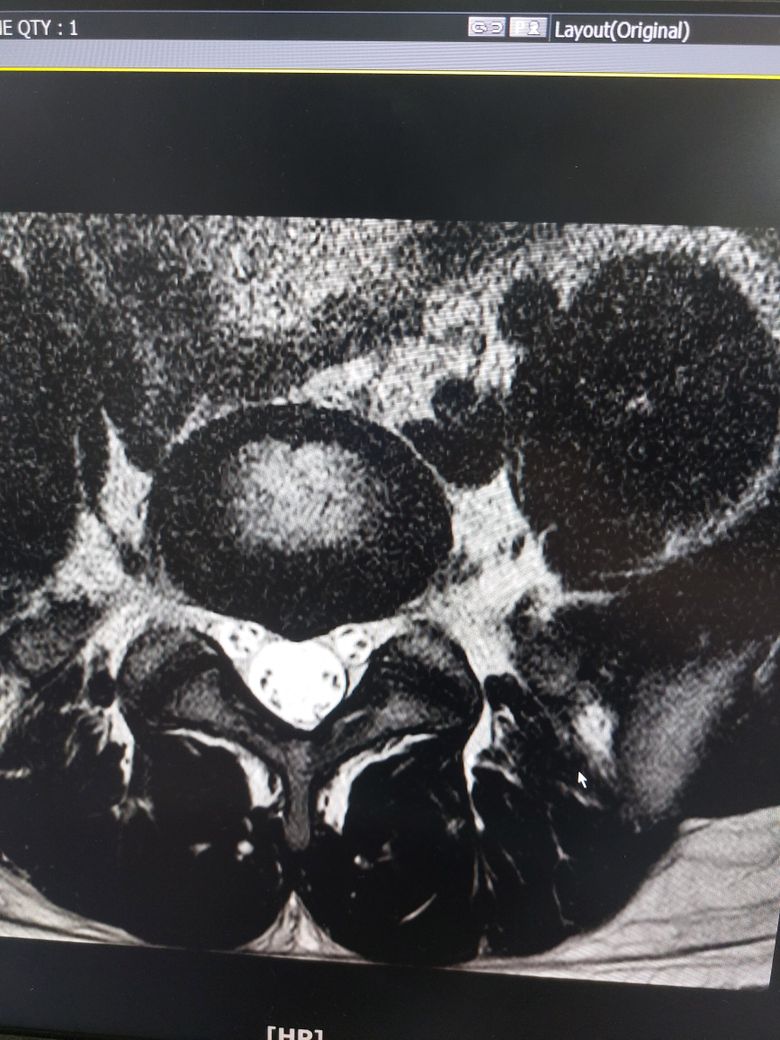

허리디스크 심한편인가요? [Mri 사진 첨부]

멸개월전부터 요추가 뻣뻣하고 시큰거리다가 최근에 좀 나아지긴 해도 만성적이라서 오늘 mri 찍고 허리디스크 진단받았습니다

(요추 맨 밑 천추 위 디스크)

Mri 찍은 병원은 고주파 시술같은거 하라고 하고 다른병원은 이정도면 잘 쉬면 완치된다고 하는데

1. 이정도면 아직 팽윤단계인가요?

2. 잘 쉬면 백프로 완치 될까요?

1. 이정도면 아직 팽윤단계인가요? 디스크 자체도 심하지 않을 뿐더러 그에 따른 증상인지 여부도 확실하지 않습니다

2. 잘 쉬면 백프로 완치 될까요? 병원마다 치료방향이 갈라진다면 가능한 몸에 무리가 가지 않는 치료를 하는 것이 좋습니다. 먼저 쉬어보세요. 그러고 경과를 지켜보시죠.